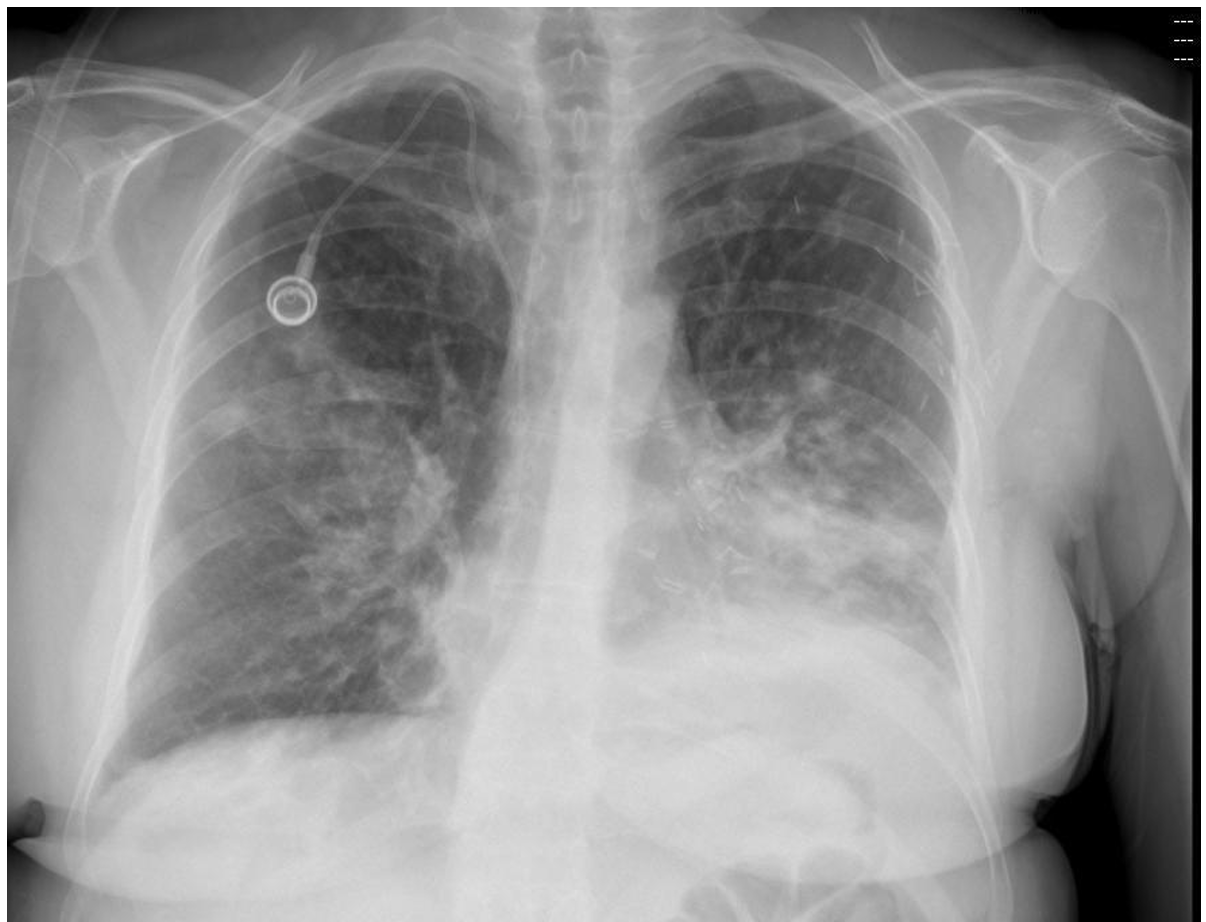

A previously well 23 year old is brought to your ED acutely short of breath after developing left sided chest pain.

A Chest xray is taken on arrival- refer to the props booklet- page 2.

a. State five (5) abnormalities shown on this xray. (5 marks)

b. List three (3) key steps in your treatment of this patient. State one (1) justification for each step. (6 marks)